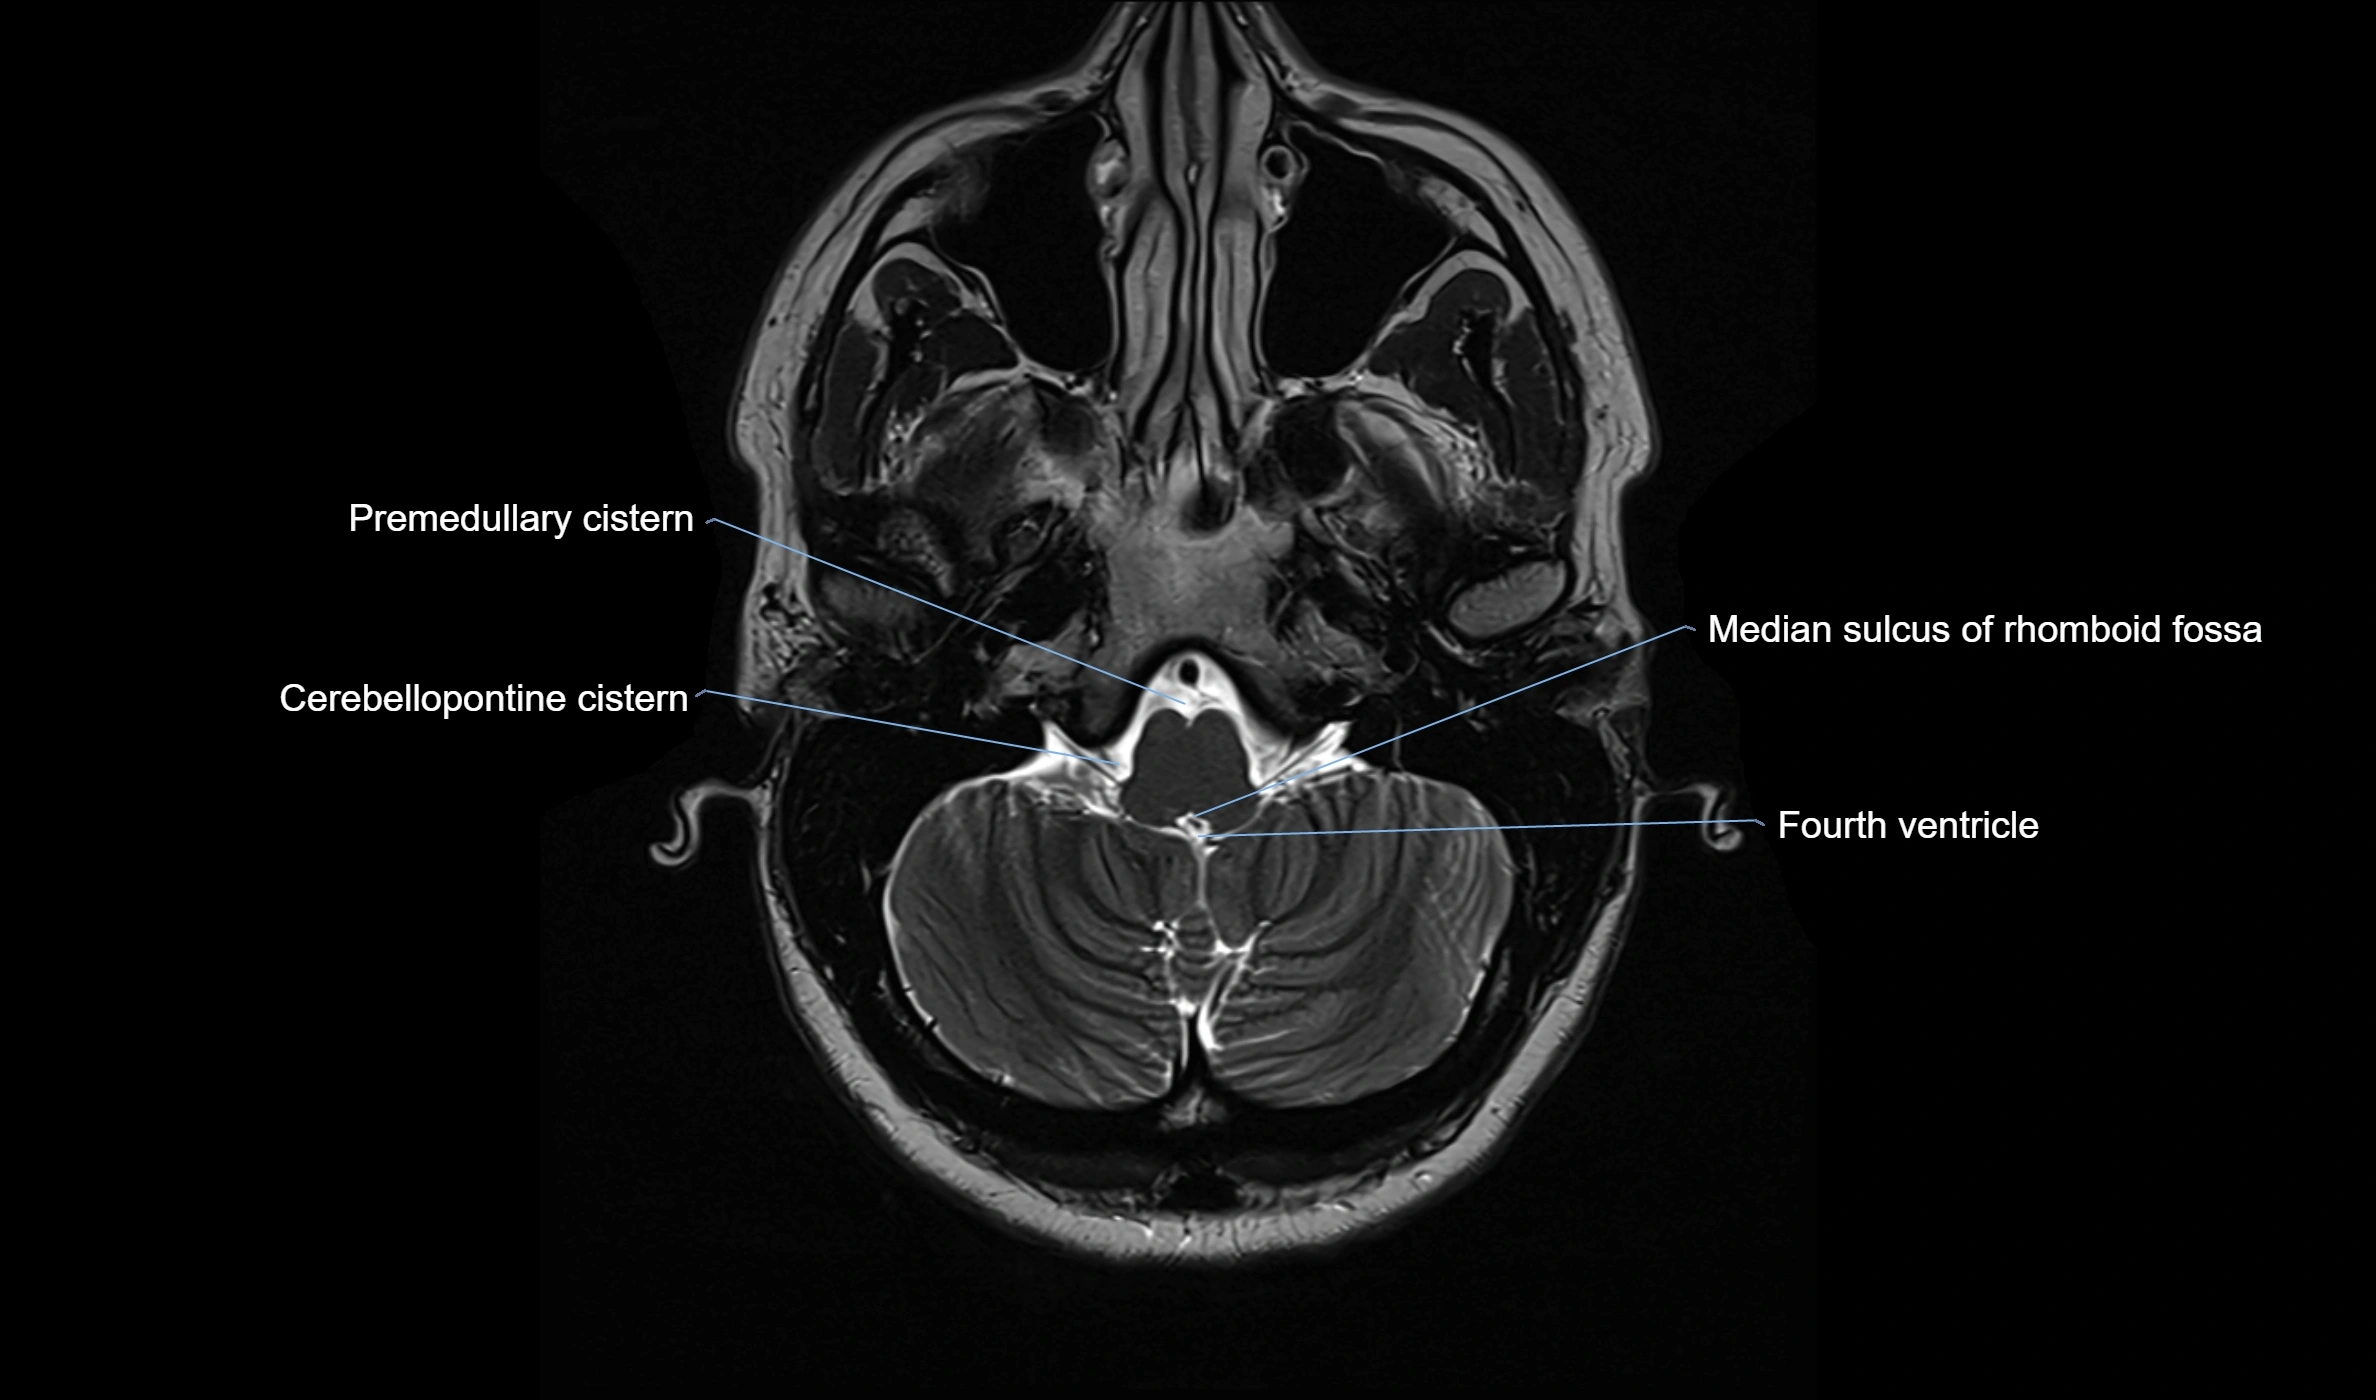

MRI images

image